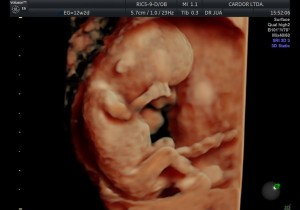

En el primer trimestre, desde la concepción hasta las 12 semanas de la gestación, se forman los principales órganos del feto: corazón, intestino, estómago…

Vea la siguiente presentación. Imágenes 100% Cardor: